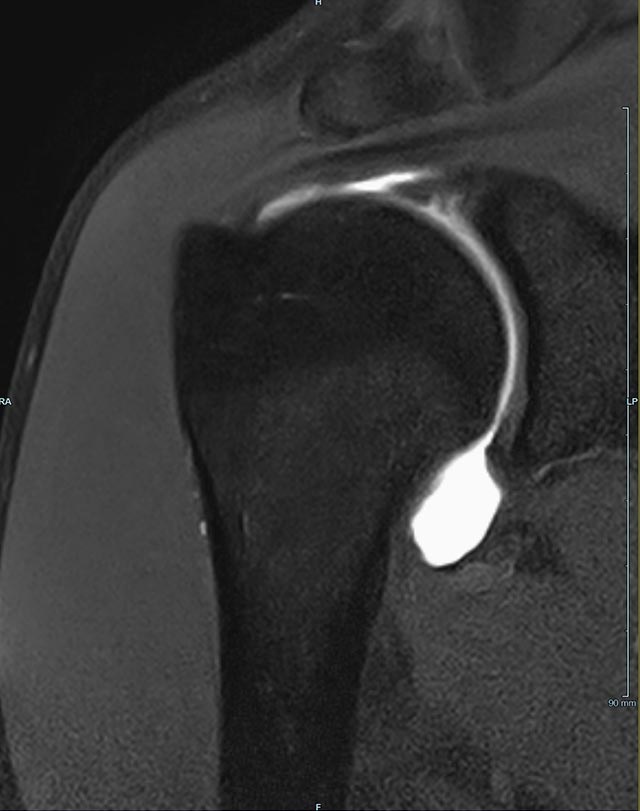

- MR-Arthrographie – nach örtlicher Betäubung und gründlicher Desinfektion der Haut wird unter Lagekontrolle mit Röntgen-Durchleuchtung eine kleine Nadel in den Gelenkraum positoniert und darüber ein MR-taugliches Kontrastmittel in den Gelenkraum gespritzt. Danach wird die Nadel entfernt. Anschließend erfolgt die MRT des Gelenkes. Diese Methode stellt kleine anatomische Strukturen des Gelenkraumes verbessert dar, z.B. zur Therapieplanung vor Arthroskopie bei Sportverletzungen der Schulter oder Gelenkinstabilität.